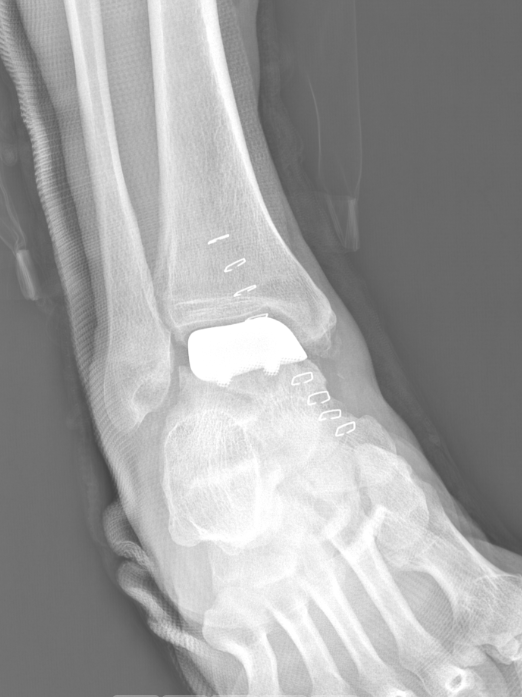

术后侧位X线

术后正位X线

武勇主任团队给他做了3D打印导板辅助下人工全踝关节置换术。

这种手术适合踝关节病严重的患者,通过替换病变的关节结构,能帮着缓解疼痛、恢复关节活动,让老人日常走路更自在些。